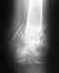

Добрый день! Закрытый диафизарный перелом костей голени, нижней трети. В данное время на вытяжке. Отек спал, были пузыри, заживают.Предлагается накостный остеосинтез пластиной с угловой стабильностью, 8 винтов. Возможен ли менее травматичный вариант, например аппаратом внешней фиксации, т.к сопутствующее заболевание - ОМЛ, 3 месяца после трансплантации костного мозга, повышен риск инфекционных осложнений. И, возможно ли в данный момент наложить гипс для транспортировки в другое учреждение? Перелому 9 дней. Извиняюсь за качество снимков; сделаны на 3 день.

• Кликните для загрузки файла IMG_20140728_134339.jpg